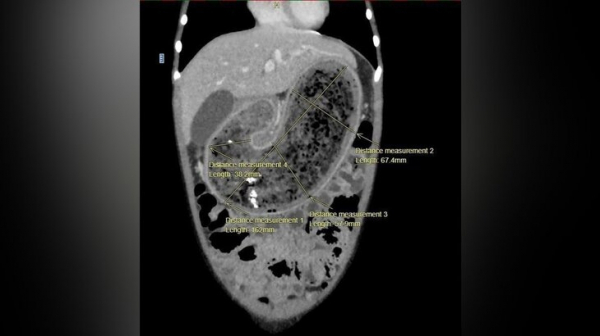

Во время первичного осмотра специалисты обратили внимание на выраженное образование в области передней стенки желудка, которое можно было прощупать. Для уточнения диагноза была проведена компьютерная томография. Исследование показало наличие огромного трихобезоара — плотного комка волос, который полностью заполнил желудок, распространился в двенадцатиперстную кишку и начальный отдел тонкой кишки. Подобные образования формируются в результате проглатывания волос, которые не перевариваются и постепенно накапливаются, склеиваясь слизью и пищевыми остатками.

Объем извлеченного образования составил около 900 миллилитров. В составе комка были обнаружены волосы, слизь, фрагменты ткани и нитки. Подобная структура подтверждает, что процесс формирования трихобезоара происходил на протяжении длительного времени. Врачи предполагают, что у девочки могла сформироваться привычка тянуть в рот собственные волосы и кусочки ткани — состояние, которое в медицинской практике связывают с психоэмоциональными факторами и стрессом.